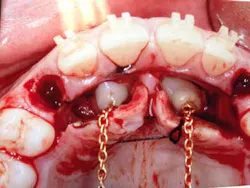

When a full permanent dentition is present (with the exception of impacted canines), the labial/palatal position of the canine will have an influence on what the provider can do. (1) Arguably, obtaining a CBCT is considered mandatory and will allow for a more inclusive treatment plan creation. If angulation is favorable, then consideration to remove the primary canine and wait six months to see if there is movement of the permanent canine is an option. If extraction of the canine(s) is needed, then a premolar substitution, which is dependent on occlusion, can be used in the space. An implant can also be an appropriate alternative. When pulling a canine into the occlusal arch, there is risk involved. Trauma to adjacent teeth (root resorption) and ankylosis are some of the most common complications.The patient was put in full orthodontics and referred to a surgeon for extraction of the primary canines, exposure, and placement of retention on the impacted canines to pull them directly down from their current position.

A ballista appliance was used to prevent a facial pull of the canines in order to avoid and prevent resorption of the roots of the lateral incisors. As movement progressed over the course of the next year, eruption of the canines was considered a success. Once in position, they will be pulled facially into occlusion.